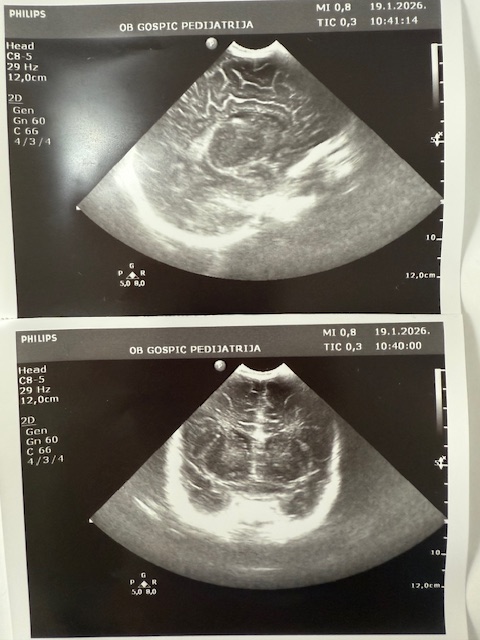

Dječji odjel opće bolnice Gospić jedan je od manjih u Hrvatskoj, ali izuzetno aktivan. Uz redovnu djelatnost, ambulante, Dnevne bolnice i vođenja samog Odjela kao i Rodilišta što obavljaju tri liječnice specijalisti pedijatrije (Sandra Čubelić, dr.med., Linda Hibravi Kosić, dr.med. i Kristina Ilić, dr.med.), pri Odjelu radi i Ultrazvučna ambulanta u kojoj se već 20 godina jedini u Hrvatskoj radi dojenački probir na bolesti i razvojne poremećaje mozga i razvojni poremećaj zgloba kuka. Dakle naglašavamo da svako dojenče rođeno u Općoj bolnici Gospić obavi oba ova pregleda po principu “skrininga”, što znači da se traže poremećaji kod zdrave djece.

Probir radi pedijatrica i ravnateljica bolnice, dr. Sandra Čubelić, a analizom je utvrđeno kako se uz ovaj nadstandard koji imaju djeca Ličko-senjske županije godišnje odradi oko 1200 ultrazvučnih pregleda, odnosno tijekom ovih 20 godina učinjeno je oko 25000 pregleda. U početku su se pregledi radili još u novorođenačkoj dobi, a sada je uobičajeno napraviti pregled dojenčadi u dobi od 1 mjesec. Svrha navedenog je otkriti poremećaj prije nego što se kod djeteta pokažu simptomi i znakovi bolesti stoga valja istaknuti da je kod dvoje djece izvedena operacija mozga prije nego je dojenče imalo ikakve poremećaje u smislu smetnji psihomotornog razvoja dok različite se manje razvojne poremećaje nađe bitno češće.

Što se tiče zgloba kuka, razvojni poremećaji se graduiraju pa se teži poremećaji kao što je luksacija i subluksacija nađu rjeđe, dok se poremećaji u smislu displazije nađu češće, a svrha ovih pregleda je da se izliječe prije prohodavanja djeteta jer poremećaji koji se uoče nakon što dijete prohoda se teže i dugotrajnije liječe, čak i operativno.